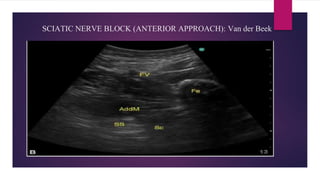

SCIATIC NERVE BLOCK (ANTERIOR APPROACH): Van der Beek

• This is an advanced block, as the nerve is deep and not easily visualized in most

patients.

• Patient supine, legs slightly abducted.

• Place a low-frequency (3–5 Mhz) curved probe perpendicular to the axis of the thigh,

5–10 cm distal to the inguinal crease.

Techniques to locate the sciatic nerve:

• Drawing an imaginary isosceles triangle with the femur as its apex, the

femoral vessels as one corner, the sciatic nerve will lie at the other

corner